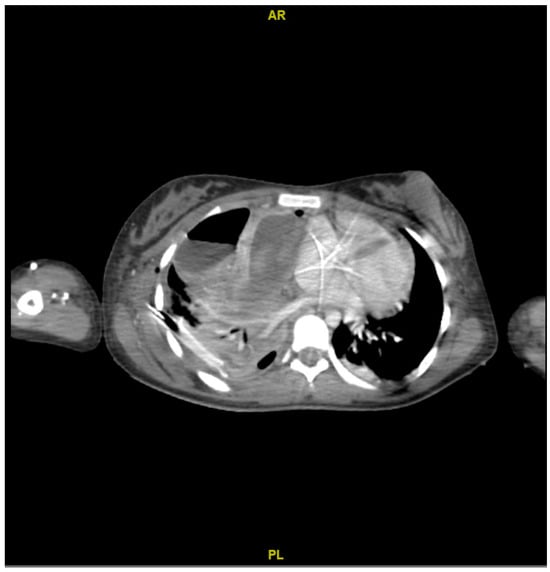

On the other hand, the computed tomography (CT) scan showed a loculated fluid collection on the entire right lung parenchyma, pneumothorax of the right upper lobe, and thickening of the right sternocleidomastoid muscle (Figure 2).

Figure 2. Contrasted computed tomography. Abscessified collection with hydroaeric levels, atelectasis of the parenchyma, lower zone consolidation, loculation in the base, and occlusion of the pleurostomy.